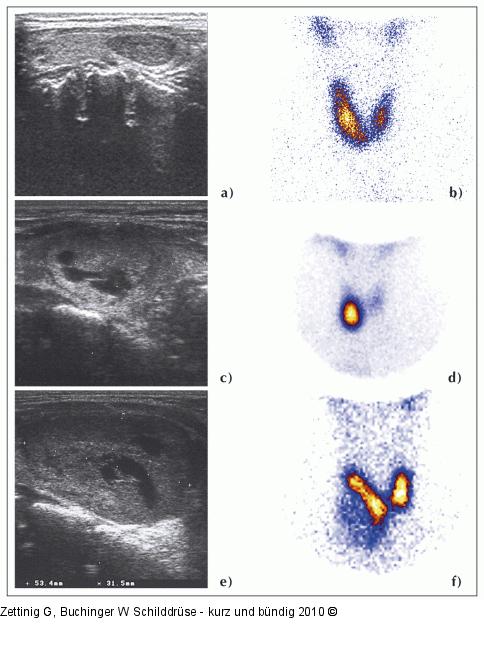

Abbildung 4a-f: Knotenstruma

Beispiele verschiedener Befunde bei Patienten mit Knotenstruma: Zur Beurteilung der Knoten sind sowohl die Sonographie als auch die Szintigraphie unerlässlich. Patient 1: Der rechts gelegene sonographisch echoarme, solide Knoten kommt szintigraphisch „warm“ zur Ansicht (a, b). Patient 2: Der sonographisch größtenteils echogleiche Knoten hat einen echoarmen Randsaum (Halo) und ist teilweise zystisch degeneriert. Szintigraphisch kommt er „heiß“ zur Ansicht, im restlichen Schilddrüsenparenchym ist die Aktivitätsbelegung vermindert: Unifokale funktionelle Autonomie (c, d). Patient 3: Der sonographisch fast den gesamten rechten Lappen einnehmende Knoten zeigt einzelne echoärmere Anteile und ist ebenfalls zystisch degeneriert. Er stellt sich szintigraphisch „kalt“ dar (e, f). |